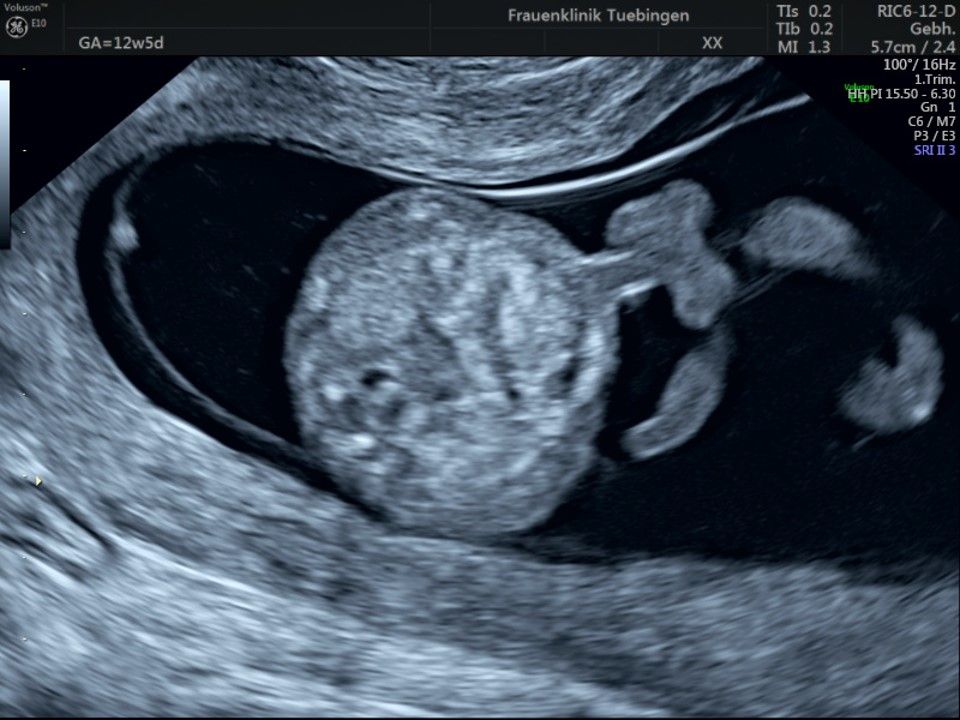

Bauchwanddefekt

Obwohl der Fet zu diesem Zeitpunkt erst zwischen 5 und 8cm groß ist, lassen sich bereits etwa die Hälfte aller schwerwiegenden Fehlbildungen erkennen bzw. ausschließen. Sollten wir eine Auffälligkeit sehen, werden wir mit Ihnen den Befund und das weitere Vorgehen ausführlich besprechen.

Es sollte berücksichtigt werden, dass strukturelle/anatomische Fehlbildungen (z.B. angeborene Herzfehler) deutlich häufiger auftreten. Bei etwa 2-3% (1:30 - 1:50) der Feten werden Fehlbildungen gefunden. Diese können isoliert, d.h. ohne Chromosomenstörung auftreten. Sie werden aber gehäuft bei Trisomien und andersartigen Veränderung des Erbguts gefunden. Daher ist eine detaillierte Ultraschalluntersuchung im Rahmen der Risikobeurteilung unerlässlich. Sollte eine Fehlbildung erkannt werden, so ist eine Risikoberechnung für Trisomie 21 alleine nicht ausreichend. Hier sollte eher an eine Fruchtwasser- oder Mutterkuchenpunktion gedacht werden, um eine Chromosomenstörung erkennen oder ausschließen zu können.